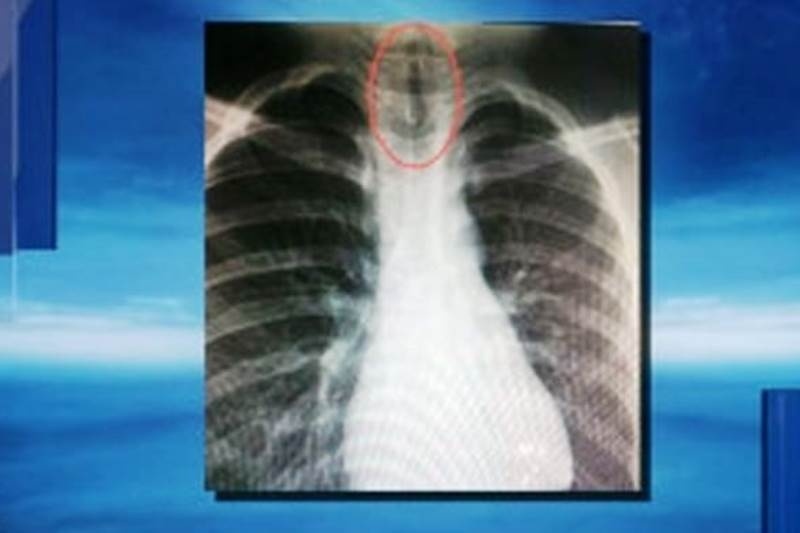

Ο μικρός Xiaobo Chien μιλούσε με τη μητέρα του και ξαφνικά άρχισε να αναπνέει με δυσκολία και αφού έπιασε το λαιμό του λιποθύμησε, με τη μητέρα του να τον πηγαίνει αμέσως στο νοσοκομείο.